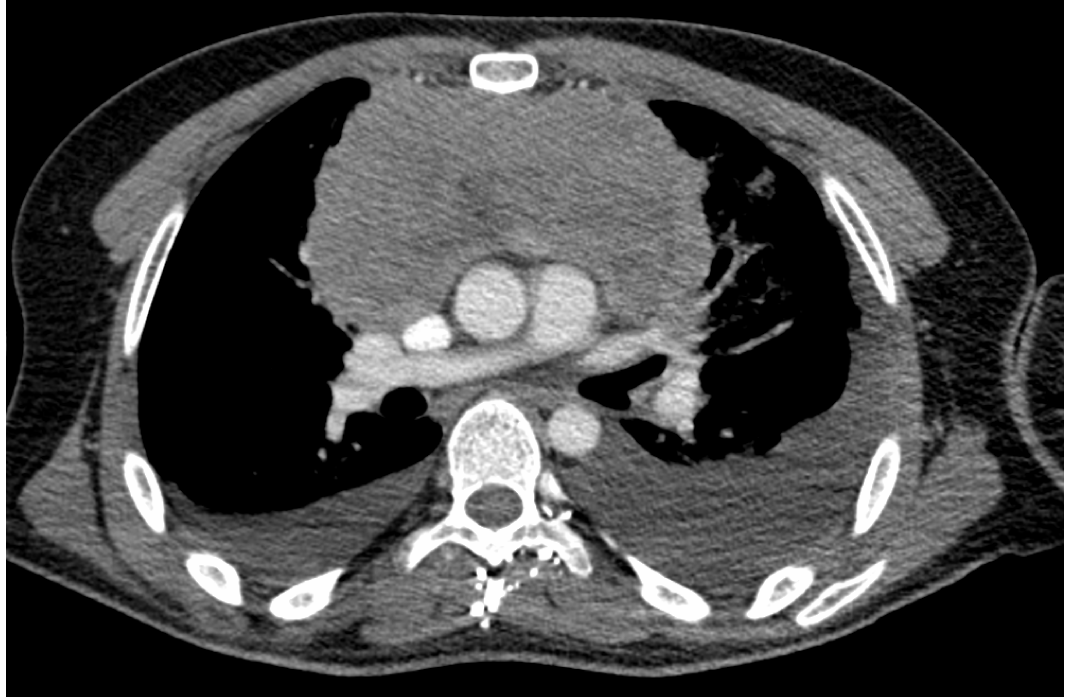

Síndrome de vena cava superior